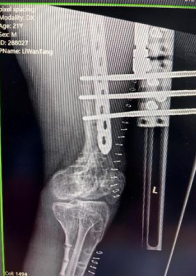

患者左股骨与胫骨骨折术后X光检查结果

说起李先生的病情,还要追溯到九年前的一场意外。在那场意外中,李先生左股骨与胫骨严重骨折,虽然在当地医院接受了手术治疗,但术后李先生小腿逐渐短缩畸形。这一变化不仅限制了他的日常活动,更是让他的生活笼罩在一层无形的阴影之中,极大地损害了心理健康。